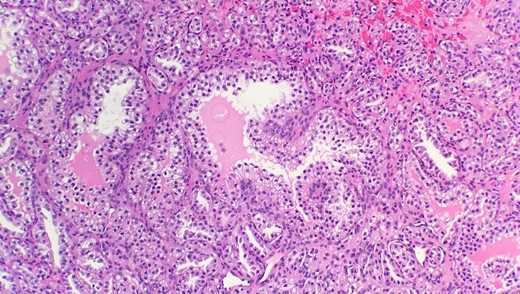

Pathological diagnosis confirmed CCPRCC. Grossly, the partial nephrectomy specimen measured 4 × 3.1 × 2.2 cm. The attached fatty tissue surrounding the kidney measured 10.5 × 7.8 × 2.5 cm. Cut sections showed a tan pink nodule with foci of white tan tissue measuring 3.5 cm. Microscopic examination reveals that the tumor is composed of cystic, tubular, solid and papillary components with clear cells and a low nuclear grade (Fig. 1). Tumor cells were also positive for CK7 (Fig. 2) and negative for CD10 (Fig. 3) and p504s supporting the diagnosis of CCPRCC.

Microscopic examination reveals that tumor is composed of mixture of cystic, solid and papillary components clear cells with low nuclear grade (HE stain 20x).